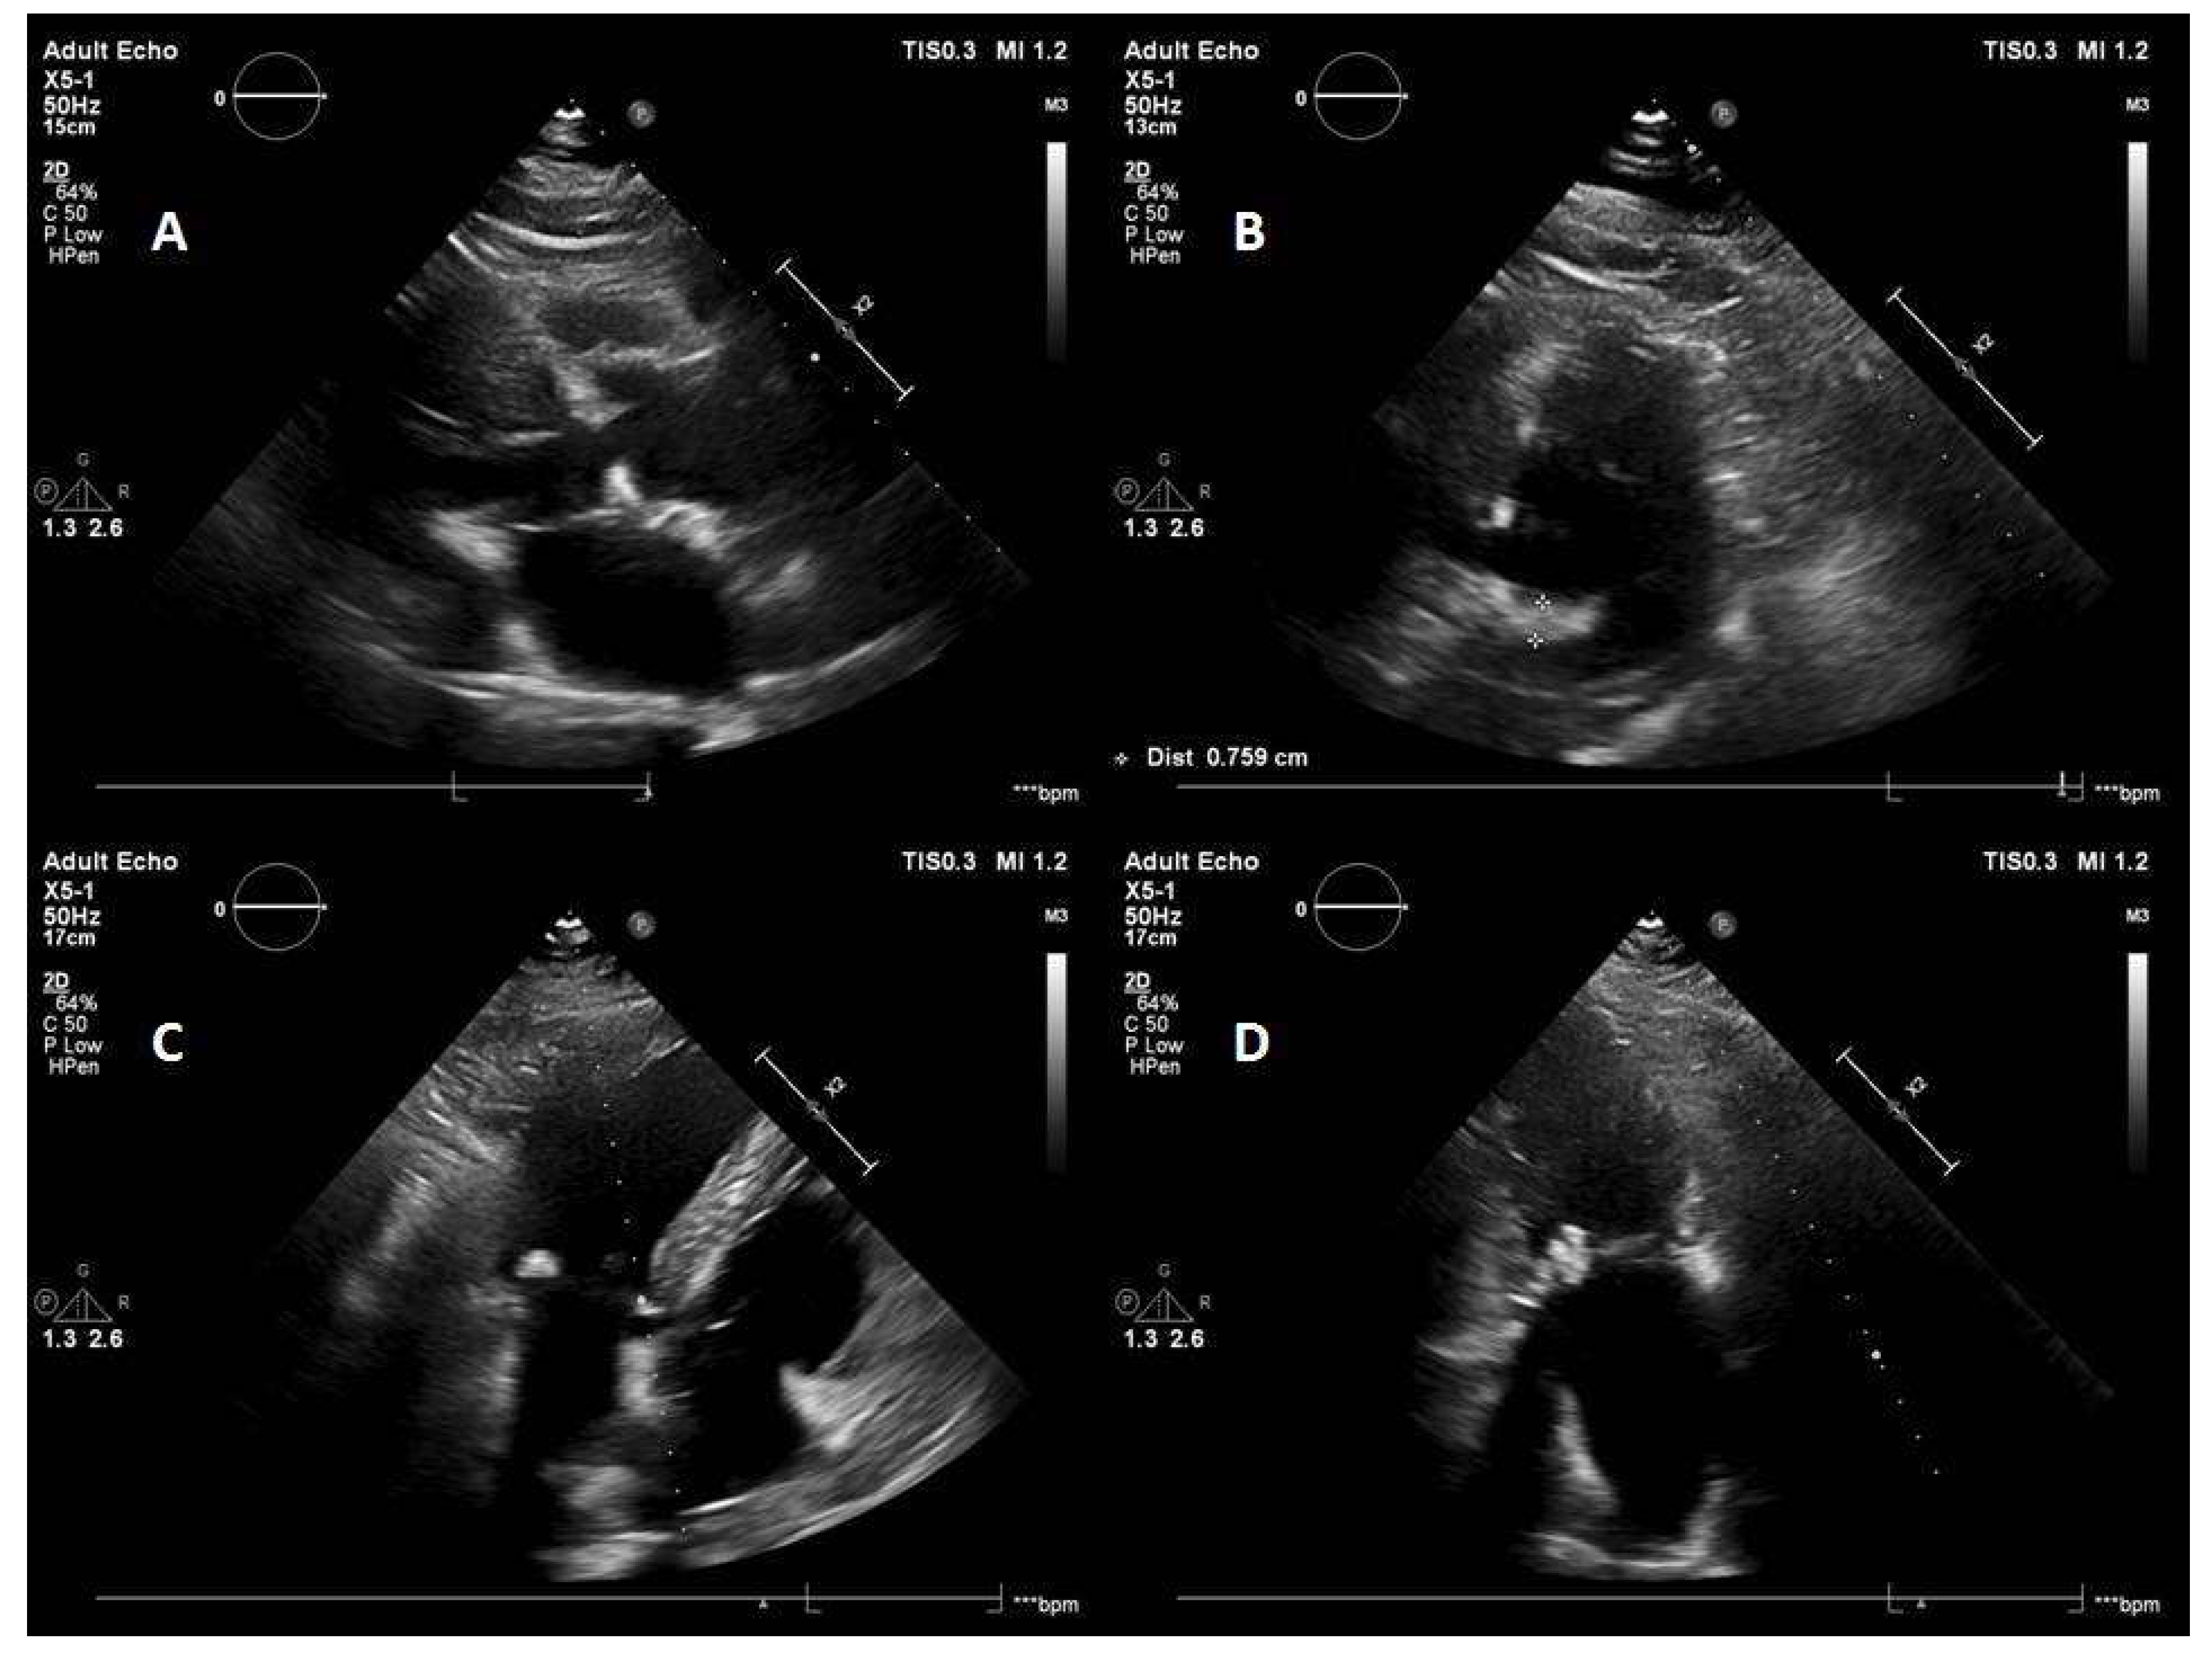

5.1. Case